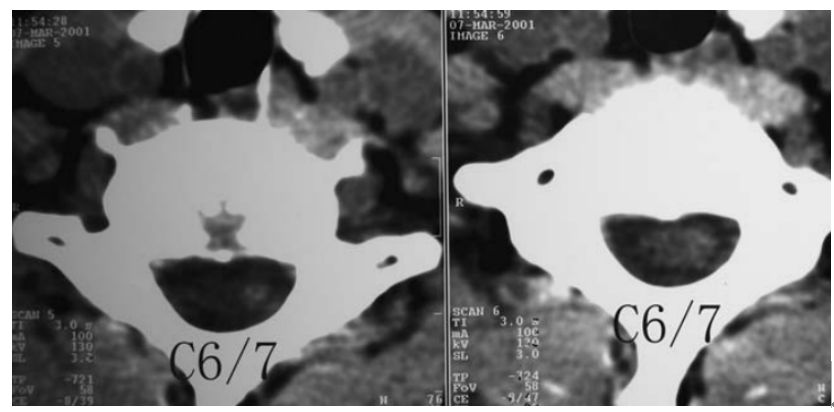

图:患者8岁,女孩,因严重颈部疼痛、活动受限伴左上肢无力、麻木不适2天就诊。既往有锁骨骨折、额部软组织挫伤病史。查体:颈椎活动受限,左上肢肌力正常,但感觉减退。白细胞、血沉、CRP升高。颈椎侧位片和CT平扫提示C6-7椎间盘钙化(粗箭头)和后纵韧带骨化(细箭头),颈椎MRI提示C6-7水平脊髓明显受压。给予颈椎制动、枕颌带2.5kg颈椎牵引2周。随后,颈托固定1个月。2年后随访复查颈椎CT如下图,同时上述症状完全缓解。

图:2年后复查CT示C6-7钙化的椎间盘和后纵韧带骨化都消失了